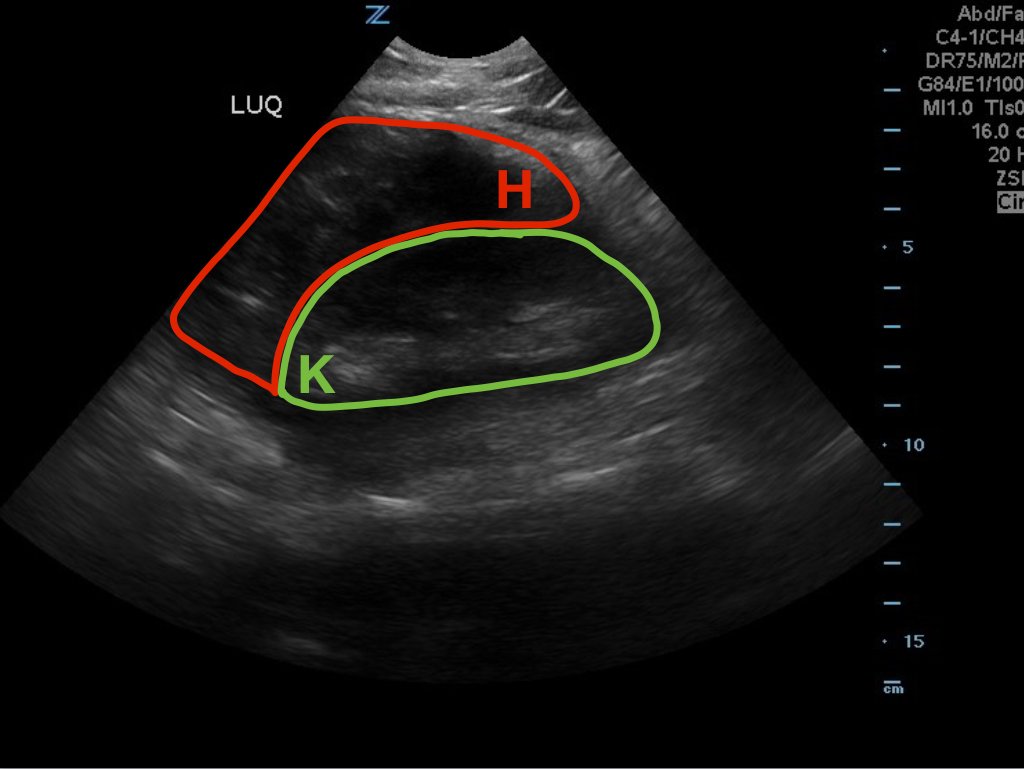

A 49-year-old male presents for evaluation of hematuria and left flank pain after mechanical fall down stairs four days ago. Point-of-care ultrasound (POCUS) focused assessment with sonography in trauma (FAST) exam demonstrated subcapsular renal hematoma. Once a subcapsular hematoma is recognized the provider should keep in mind that this condition may be managed conservatively in patients with two normally functioning kidneys, but may require urgent intervention if the patient is at risk for significant renal disease, such as a single kidney. The use of bedside ultrasound can expedite diagnosis and care for these patients, and allow proper consultants to be contacted early. Some consultants that may need to be consulted include nephrology, urology, and/or internal medicine. This case report emphasizes the utility of the FAST exam for patients presenting for non-acute trauma. The FAST exam can be utilized not only to identify free fluid in the abdomen and pelvis but also to visualize organs and the surrounding tissues for abnormalities after a trauma.